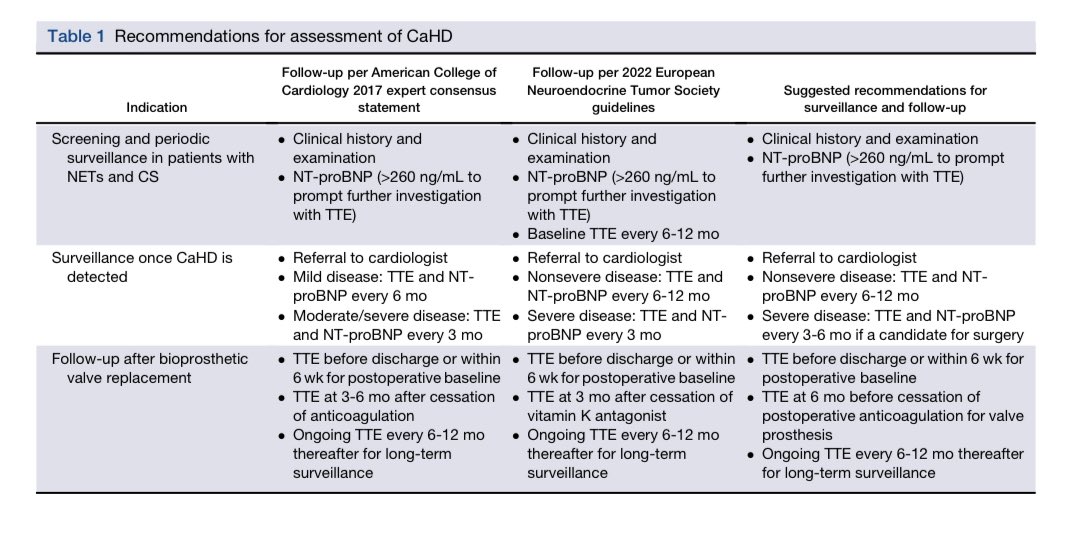

🔵 Echocardiographic Evaluation of Carcinoid Heart Disease @JournalASEcho #Cardiology #CardioEd #echofirst #FOAMed